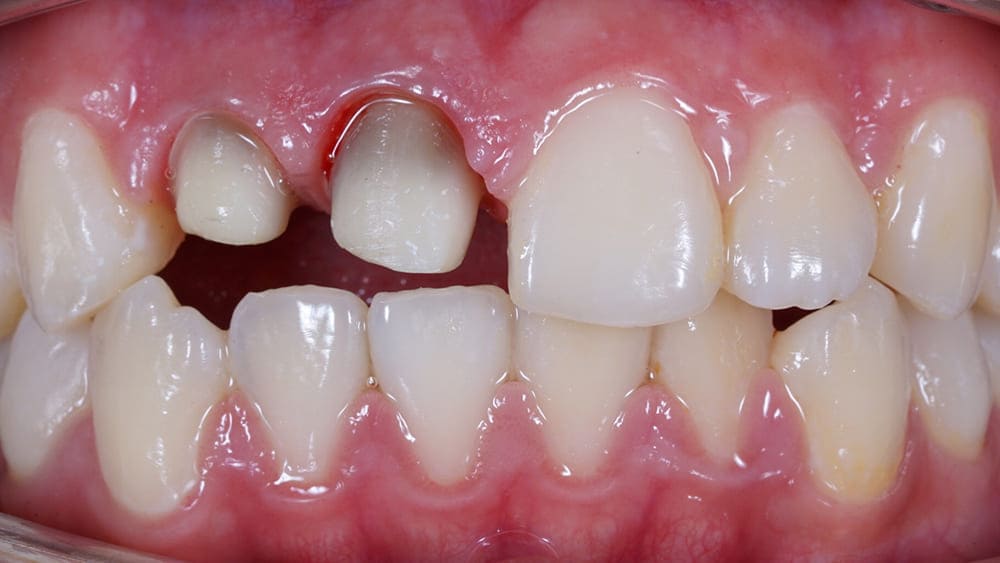

- со временем возможно изменение цвета десны в районе шейки зуба – металл, окисляясь, изменяет розовый цвет десны.

Есть много предложений в Москве с низкой ценой на металлокерамические коронки. Однако эти коронки изготавливаются без плечевой массы. Нижняя часть таких моделей (шейка зуба) окаймлена темной линией. Это придает крайне неприглядный вид. В нашей клинике, наравне с обычными металлокерамическими коронками, вы можете заказать коронки с плечевой массой. Особенные пропорции составляющих коронки обеспечивают комфортное ношение изделия, не провоцируют раздражение и изменение цвета десен, их травмирование.